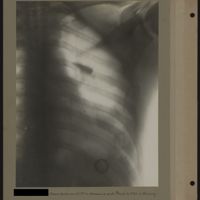

0041 - Page 37 - [Radiographies du thorax et du coude]0041 - Page 37 - [Radiographies du thorax et du coude]